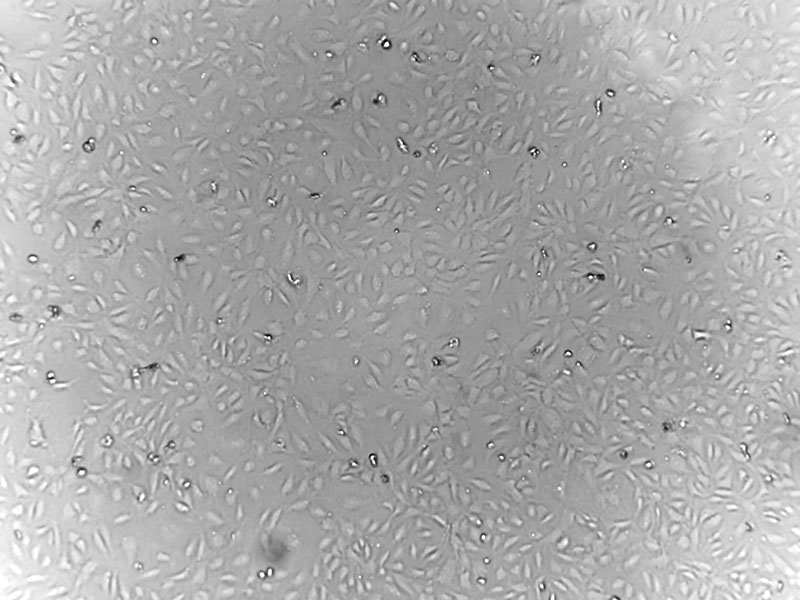

Human primary skeletal muscle microvascular endothelial cells serve as an ideal model for in vitro studies of the biology and biochemistry of endothelial cells. Theyare used in various research applications, including endothelial dysfunction, skeletal muscle regeneration, and interactions with other skeletal muscle cells, like satellite cells.

Human Skeletal Muscle Microvascular Endothelial Cells (HSkMECs) are specialized cells derived from the microvasculature of human skeletal muscle tissue. They are pivotal in studying vascular functions and pathologies within skeletal muscle.